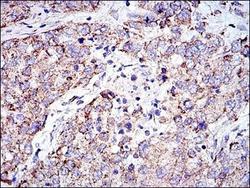

- Submitted by

- Novus Biologicals (provider)

- Main image

- Experimental details

- Immunohistochemistry-Paraffin: Prohibitin Antibody (5H7) [NBP2-37563] - Immunohistochemical analysis of paraffin-embedded rectum cancer tissues using PHB mouse mAb with DAB staining.

- Submitted by

- Novus Biologicals (provider)

- Main image

- Experimental details

- Immunohistochemistry-Paraffin: Prohibitin Antibody (5H7) [NBP2-37563] - Immunohistochemical analysis of paraffin-embedded liver cancer tissues using PHB mouse mAb with DAB staining.